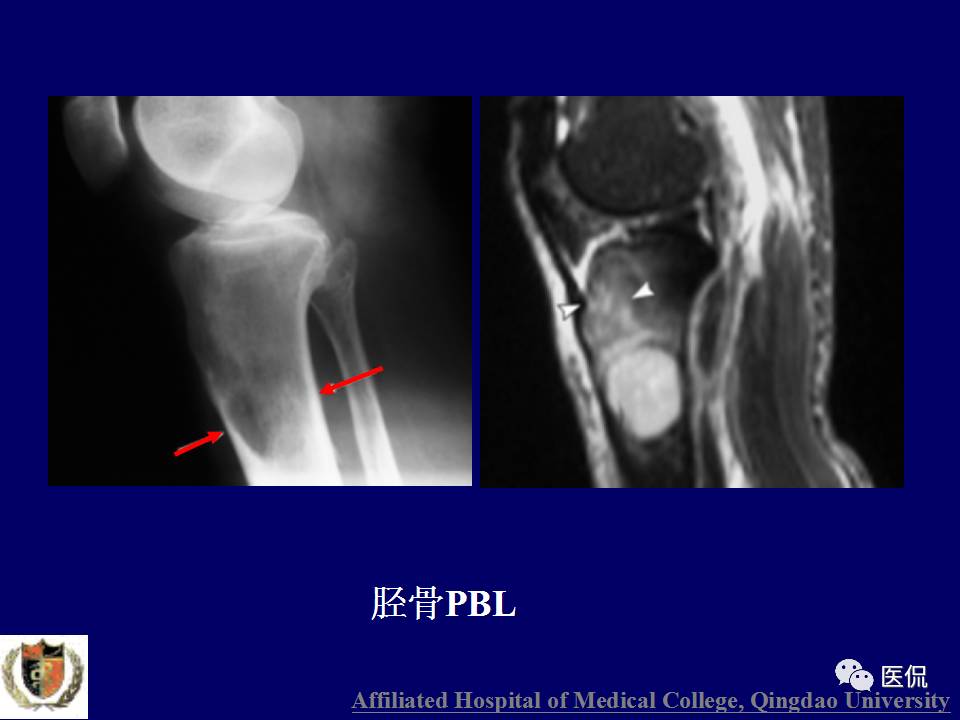

原发性骨淋巴瘤,是一种少见肿瘤。平片上干骺端单发、浸润性骨质破坏、层状骨膜反应+MR上骨髓侵犯、软组织肿块+年龄>30岁均可高度提示,影像学区分原发和继发PBL比较困难。更多知识,请往下看~